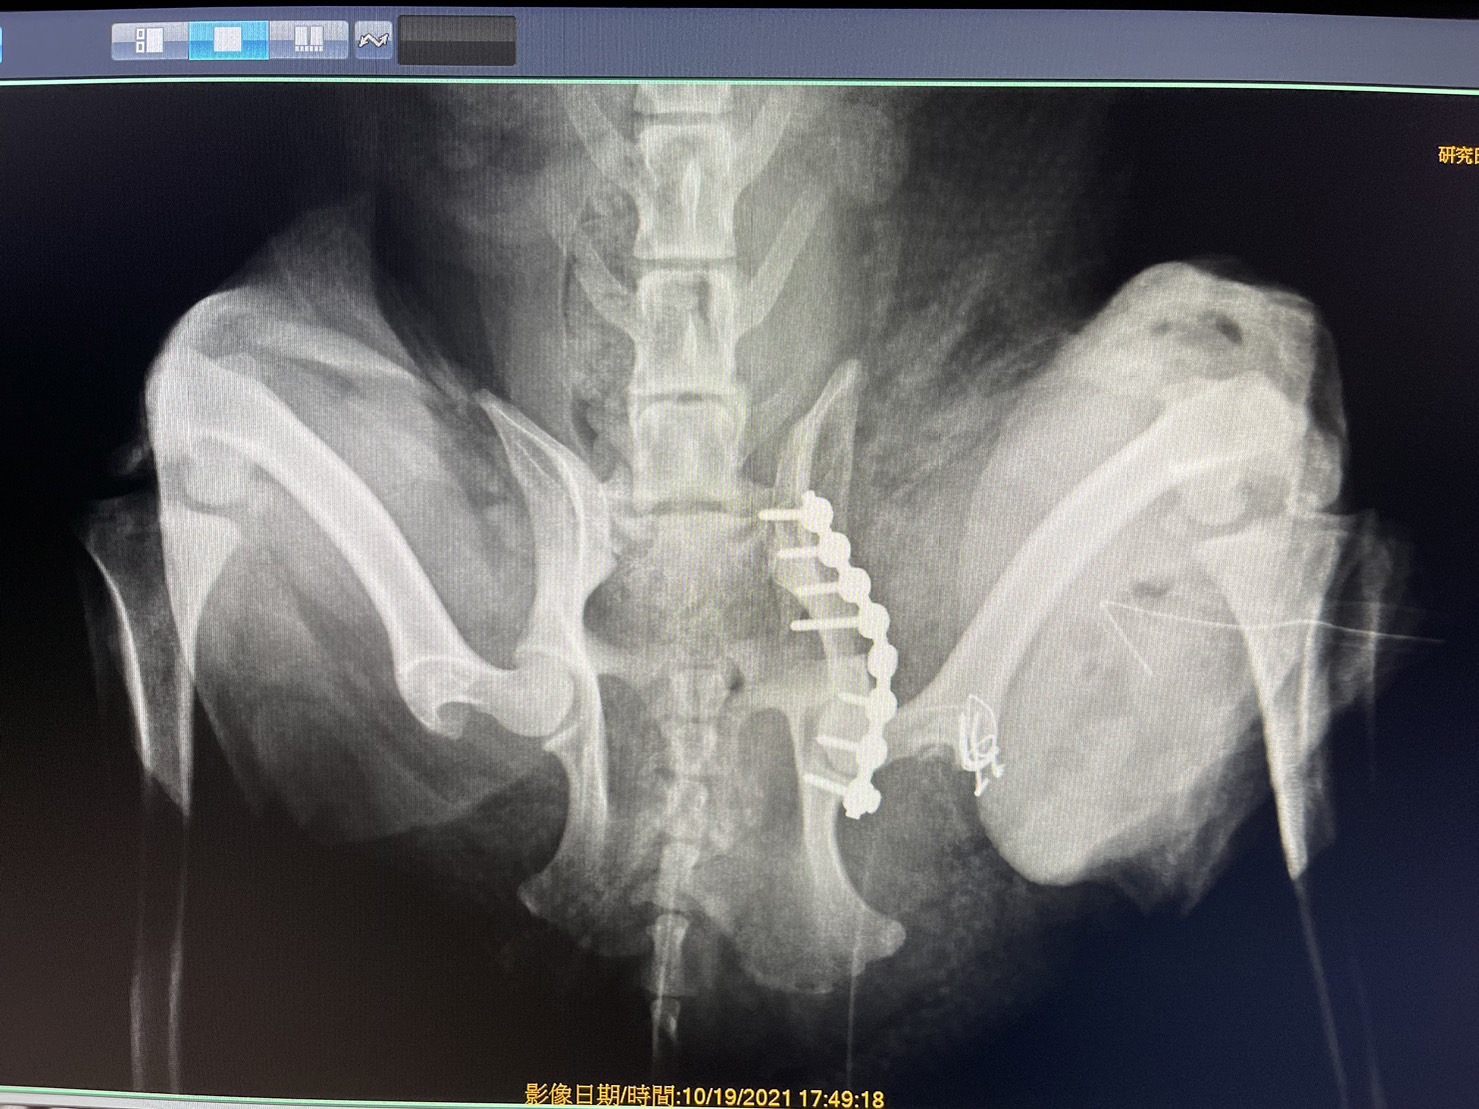

狗狗 車禍 骨盆骨折

狗狗的骨盆骨折相對於常見的四肢骨折 不容易單純靠xray 診斷及擬定手術計畫藉由電腦斷層影像的支援 能提高手術成功的機率

14kg 11歲的莓莓 術後10個月追蹤 行動自如一切正常喔

術前

術後

電腦斷層影像